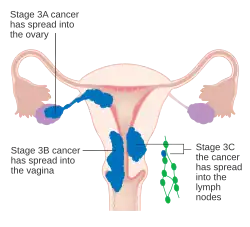

O carcinoma endometrial é estadiado cirurgicamente usando o sistema de estadiamento de cancro FIGO. O sistema de preparação do FIGO de 2009 é o seguinte:[56][57]

| Etapa | Descrição |

|---|---|

| I A | O tumor está confinado ao útero com menos da metade da invasão miometrial |

| IB | O tumor está confinado ao útero com mais da metade da invasão miometrial |

| II | O tumor envolve o útero e o estroma cervical |

| IIIA | O tumor invade a membrana serosa ou anexos |

| IIIB | Envolvimento vaginal e/ou parametrial |

| IIIC1 | Envolvimento do linfonodo pélvico |

| IIIC2 | Envolvimento de linfonodos para-aórticos, com ou sem envolvimento de linfonodos pélvicos |

| IVA | O tumor invade a mucosa da bexiga e/ou mucosa do intestino |

| IVB | Metástases distantes, incluindo metástases abdominais e/ou linfonodos inguinais |

A invasão miometrial e o envolvimento dos linfonodos pélvicos e para-aórticos são os padrões de disseminação observados com maior frequência.[2] Às vezes, é incluído um Estágio 0, neste caso denominado "carcinoma in situ".[9] Em 26% dos cancros presumivelmente em estágio inicial, o estadiamento intraoperatório revelou metástases pélvicas e à distância, tornando necessário um estadiamento cirúrgico abrangente.[25]

Cancro do endométrio em estágio II Cancro do endométrio em estágio III

Cancro do endométrio em estágio III Cancro do endométrio em estágio IV